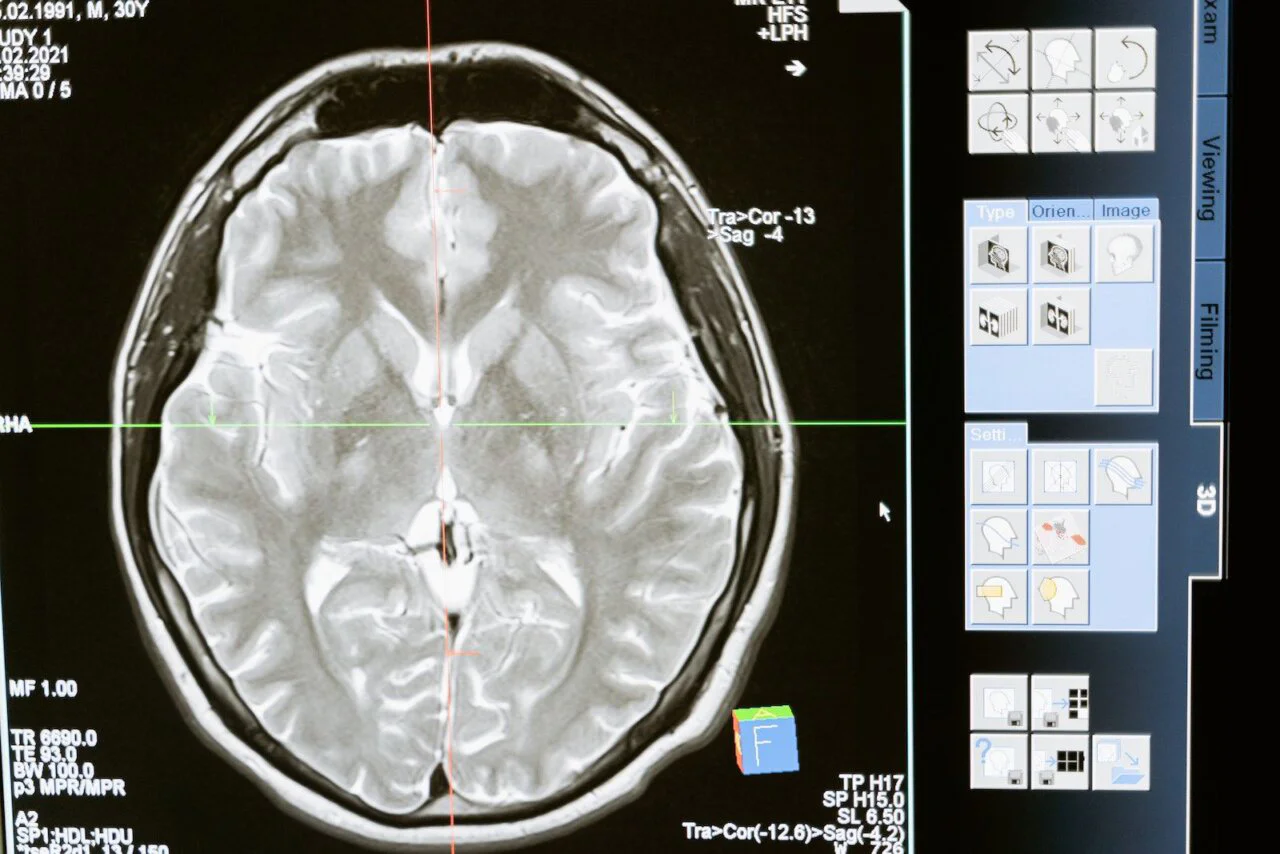

Des chercheurs américains ont réussi à transcrire les pensées en texte. Cet exploit a été possible grâce à une IA similaire à ChatGPT et à des IRMf (Imagerie par Résonance Magnétique Fonctionnelle). Une innovation technologique pour l’instant uniquement à usage médical, pour aider les personnes qui ne peuvent plus s’exprimer.

Si ce décodeur arrive à retranscrire l’activité cérébrale humaine sous forme de texte, sa mise en place de système est assez longue : trois personnes ont dû passer 16 heures à le calibrer lors des premiers tests.

Les médecins ont dû raconter des histoires a leurs patients pendant que leurs flux sanguin étaient analysés, l’objectif étant de déterminer quelles parties de leur cerveau été stimulées a ce moment précis.

Ces données ont ensuite été envoyées à GPT-1, l’ancêtre de ChatGPT, qui s’est révélé très efficace pour reconnaître les schémas cérébraux relevés par l’IRMf et les associer à des mots ou des lettres. Une fois que l’IA a analysé toutes ces données, il a été capable de retranscrire les pensées des patients.